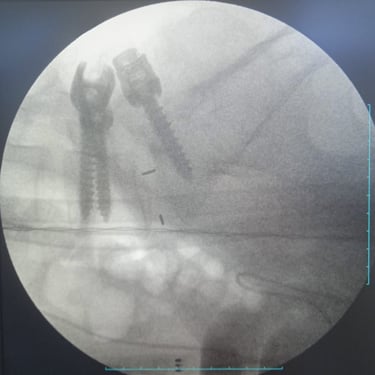

🧠 Fractura Vertebral Lumbar: Estabilización Segura con Fijación Transpedicular (FTP).

La fractura vertebral lumbar genera inestabilidad y dolor severo. La artrodesis con fijación transpedicular es una técnica quirúrgica eficaz que estabiliza la columna, previene desplazamientos vertebrales y mejora la recuperación funcional del paciente.